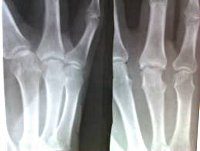

Рентгенография пальцев Рентгенологическое исследование, показанное при подозрении на переломы и вывихи фаланг пальцев, воспалительные и дегенеративно-дистрофические процессы, новообразования и гнойные процессы этой анатомической области. Стандартное исследование проводится в двух проекциях (прямой и боковой). В зависимости от характера травмы, врач может назначить рентгенографию всех пальцев и изображение одного или двух пальцев. Требуется специальное обучение. В детстве и во время родов рекомендуется заменить рентгенограмму пальцев альтернативным методом (КТ или МРТ), чтобы уменьшить или устранить радиационное облучение.

Рентгенография пальца в травматологии назначается при подозрении на переломы и вывихи фаланги. В гнойной хирургии в качестве показаний подозреваются кошачьи, наличие инфицированных ран с возможным повреждением костных структур. В ревматологии методика используется для оценки состояния мелких суставов, когда они повреждены. В ортопедии исследование проводится с дефектами развития кисти, в онкологии - с опухолевыми образованиями этого места.